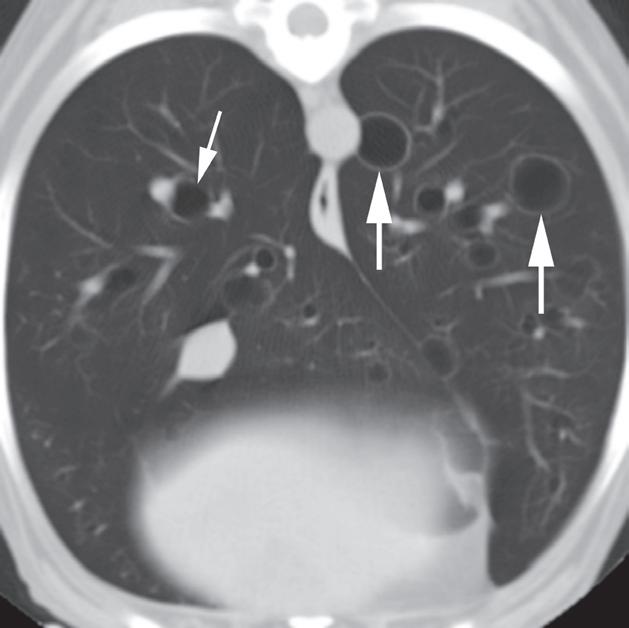

Rycina 4.6.3. Pęcherze płucne (pies) TK

Badanie wykonano u 13-letniego foksteriera z pojedynczym gruczolakorakiem płuc (nie ukazano na rycinie).

Reprezentatywne obrazy TK środkowej i doogonowej części klatki piersiowej, uporządkowane od strony doczaszkowej do doogonowej, ujawniły liczne cienkościenne pęcherze o różnej wielkości. Pęcherze były kuliste i odróżniały się od rurowatego kształtu dróg oddechowych podczas oglądania kolejnych obrazów. Miały również większą średnicę, niż można by oczekiwać w przypadku dróg oddechowych na obwodzie płuca (a–c – duże strzałki). W przeciwieństwie do pęcherzy, drogi oddechowe się rozgałęziały (c – grot strzałki) i towarzyszyły im tętnice oraz żyły płucne (b, c – małe strzałki). U tego pacjenta pęcherze nie powodowały żadnych objawów klinicznych i uznano je za rozwojowe. Ocena makroskopowa i mikroskopowa zmian z usuniętego podczas lobektomii płuca potwierdziła rozpoznanie obrazowe